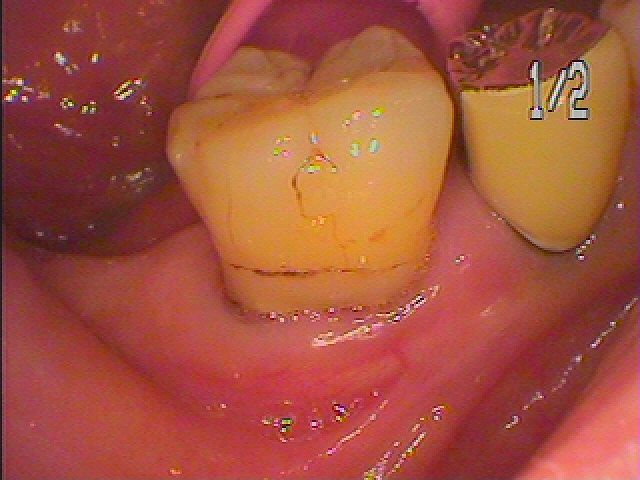

臼歯部での咬合のサポートが欠落していました

歯肉も腫れています

コンタクトも1㎜すいてきました

物がよく挟まるそうです

状態がよい時に抜歯即時インプラント埋入をさせていただきます